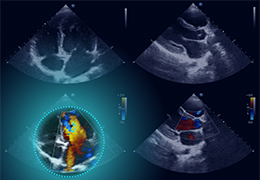

Automated Cardiac Image Analysis and Interpretation

Dyad Medical Inc. |